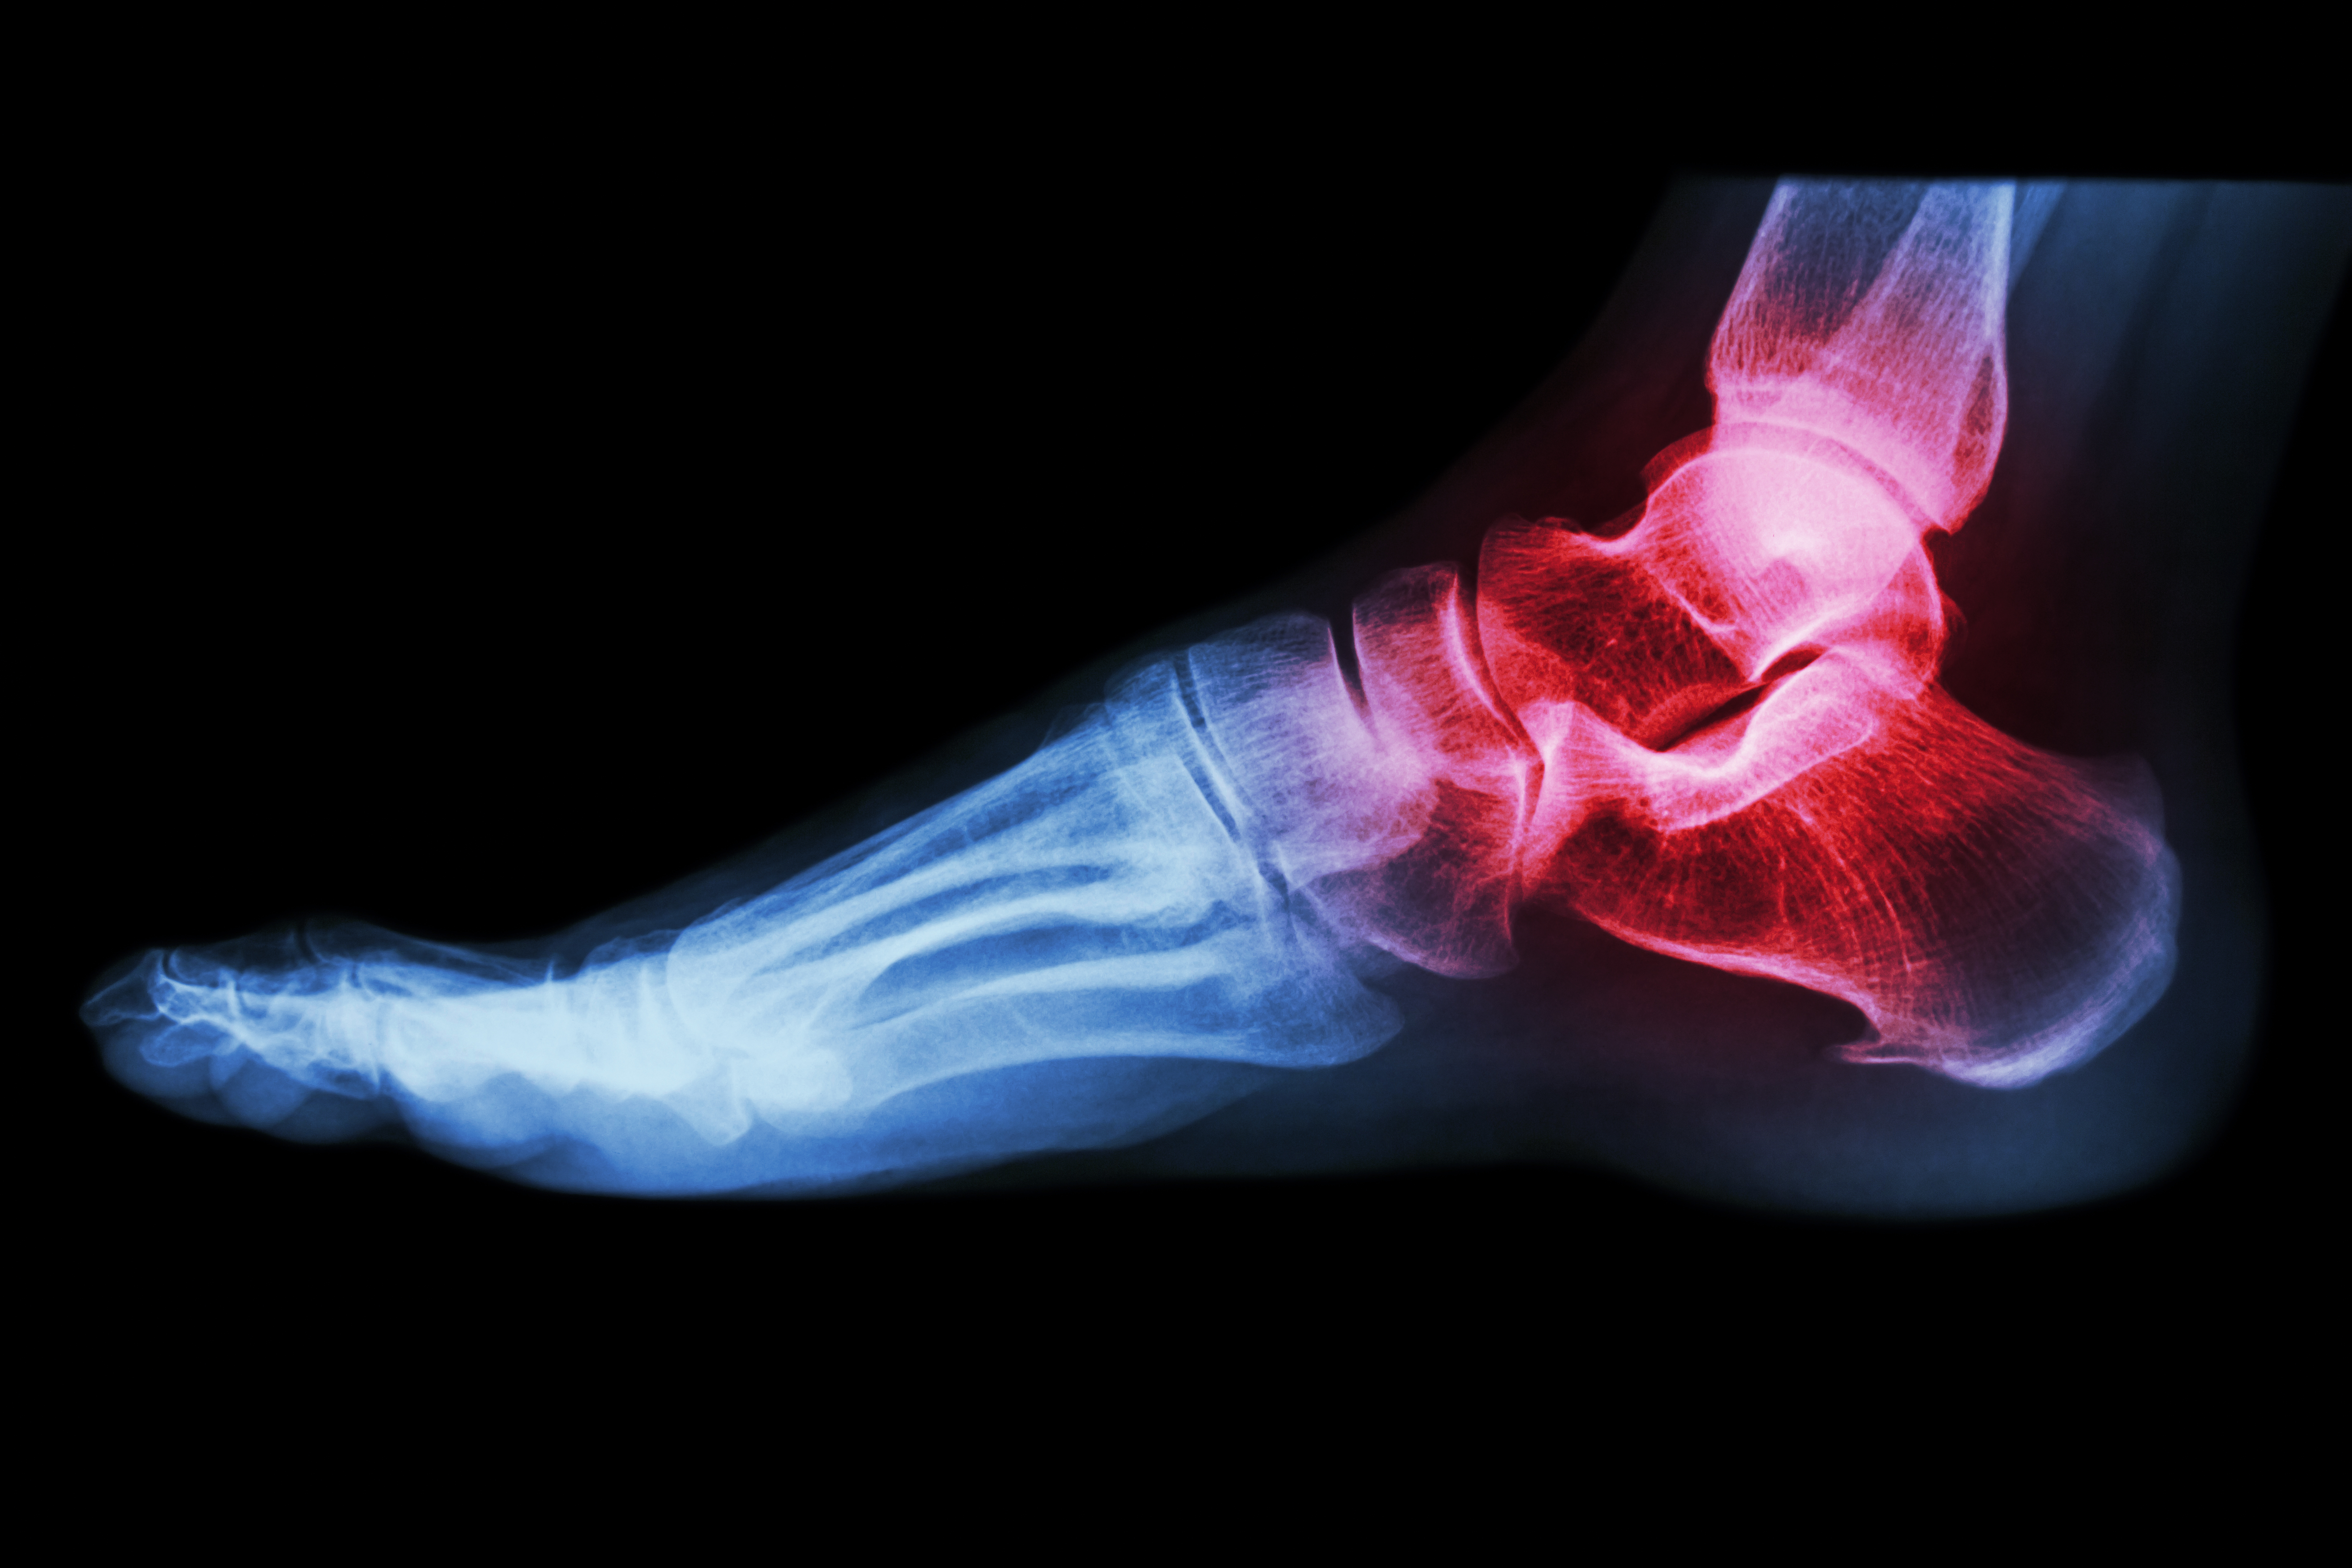

Arthritis

• Fish oil: If you have inflammatory arthritis (red, swollen joints, as in rheumatoid arthritis) add fish oil (1 teaspoon or 3 capsules 2-3 times a day for 6 weeks, then once a day).